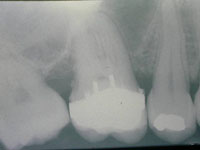

O padrão de cera foi confeccionado para a fundição com liga de ouro (Fig. 17, 18 e 19); posteriormente provou-se a infra-estrutura metálica, observando a adaptação da mesma e o espaço oclusal necessário para a aplicação da cerâmica (Ceramco III) (Fig. 20). Optou-se por cinta metálica em toda a área periférica, sendo que na palatina e nas proximais, a bainha era ligeiramente maior. Após radiografia periapical para comprovação da adaptação marginal (Fig. 21), os ajustes oclusais foram realizados em oclusão habitual, nas posições de relação cêntrica, nos movimentos cêntricos e excêntricos, a fim de se estabelecer os pontos de contato e áreas de apoio para depois se realizar o glazeamento (Fig. 22 e 23). Na Figura 24 pode-se observar o aspecto interno da restauração finalizada.

Fig. 21

Radiografia periapical para verificação da adaptação da restauração.